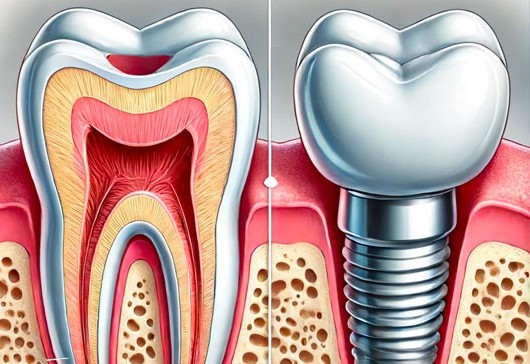

Egy megmentett fog többet ér, mint egy tökéletes pótlás?

Ma már szinte rutinszerűen beszélünk foghúzásról és implantátumról, mint gyors megoldásokról. De van valami, amit sem a legmodernebb pótlás, sem a legdrágább implantátum nem tud visszaadni: az eredeti fog természetes szerkezete és élő szövetei. A modern fogászat célja nem csupán az esztétikai helyreállítás, hanem a valódi megőrzés. A mikroszkópos technológia lehetőséget ad arra, hogy még … Egy megmentett fog többet ér, mint egy tökéletes pótlás? részletei...